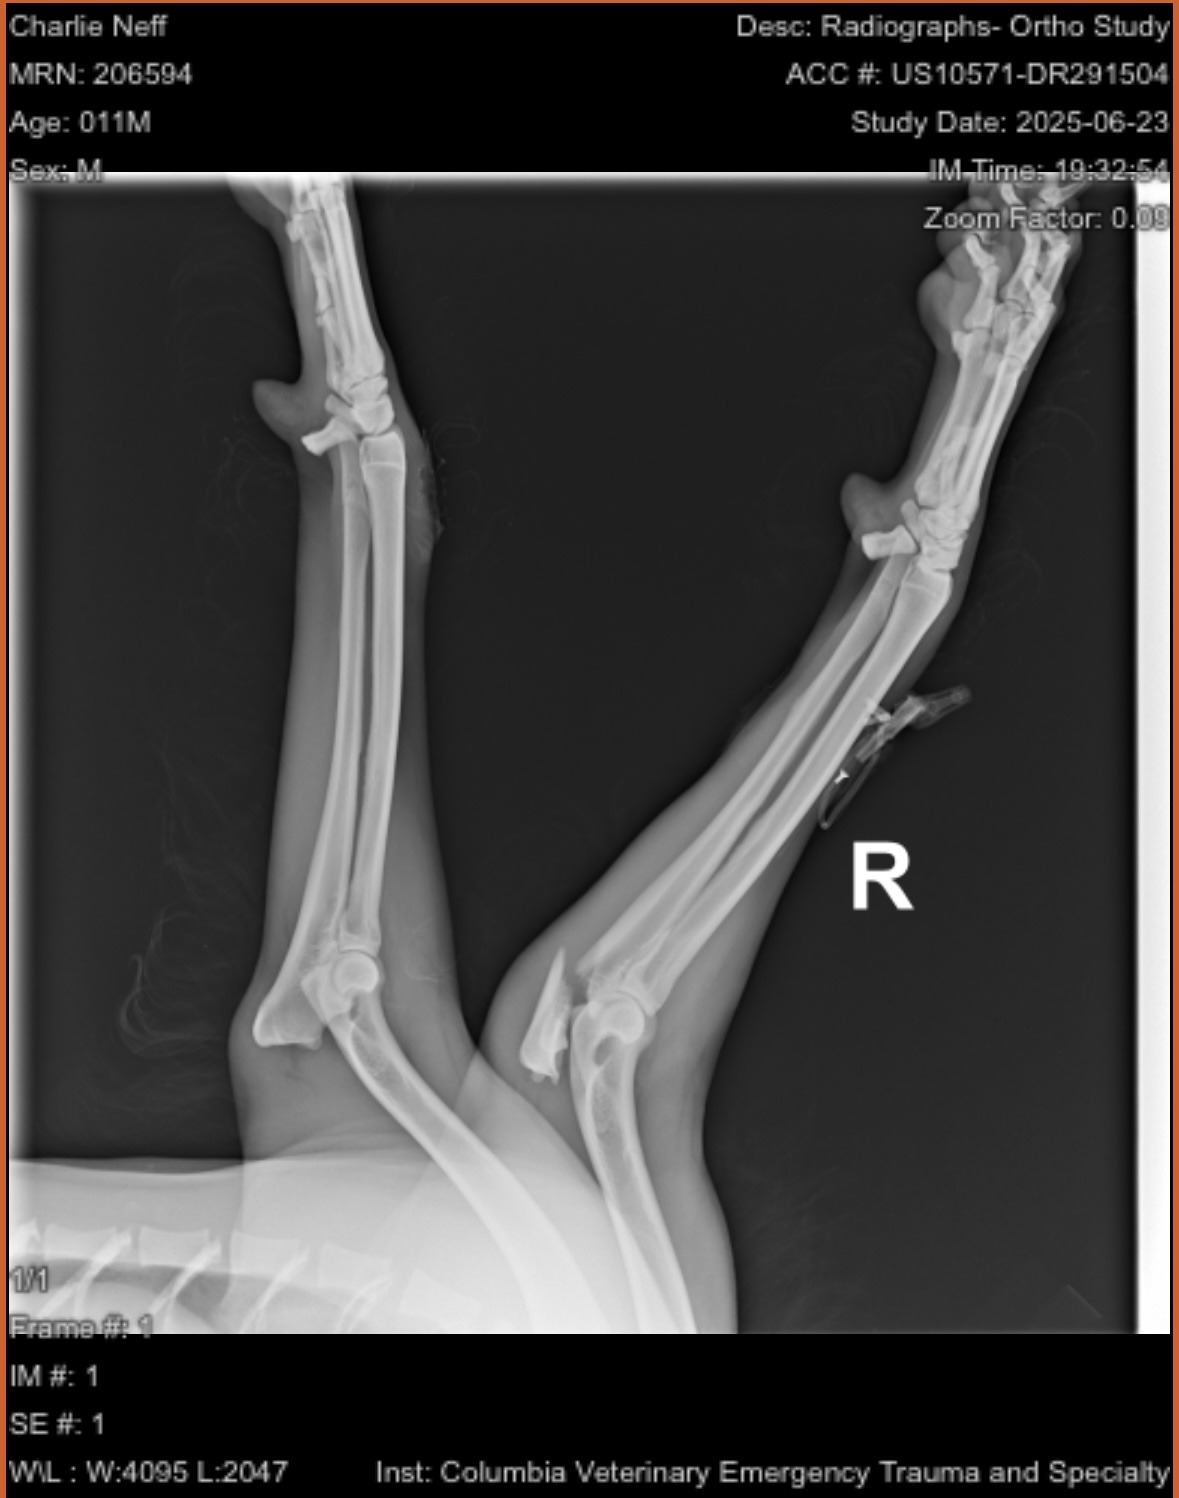

Our sweet rescue dog, Charlie, was recently the victim of a hit-and-run. He was hit by a car that didn’t stop, leaving him with a broken elbow and a dislocated hip. The injuries are severe, and without urgent surgery, Charlie may never walk properly again—or worse. The cost for his surgery and care is estimated at $8,000, which we simply can’t cover on our own.